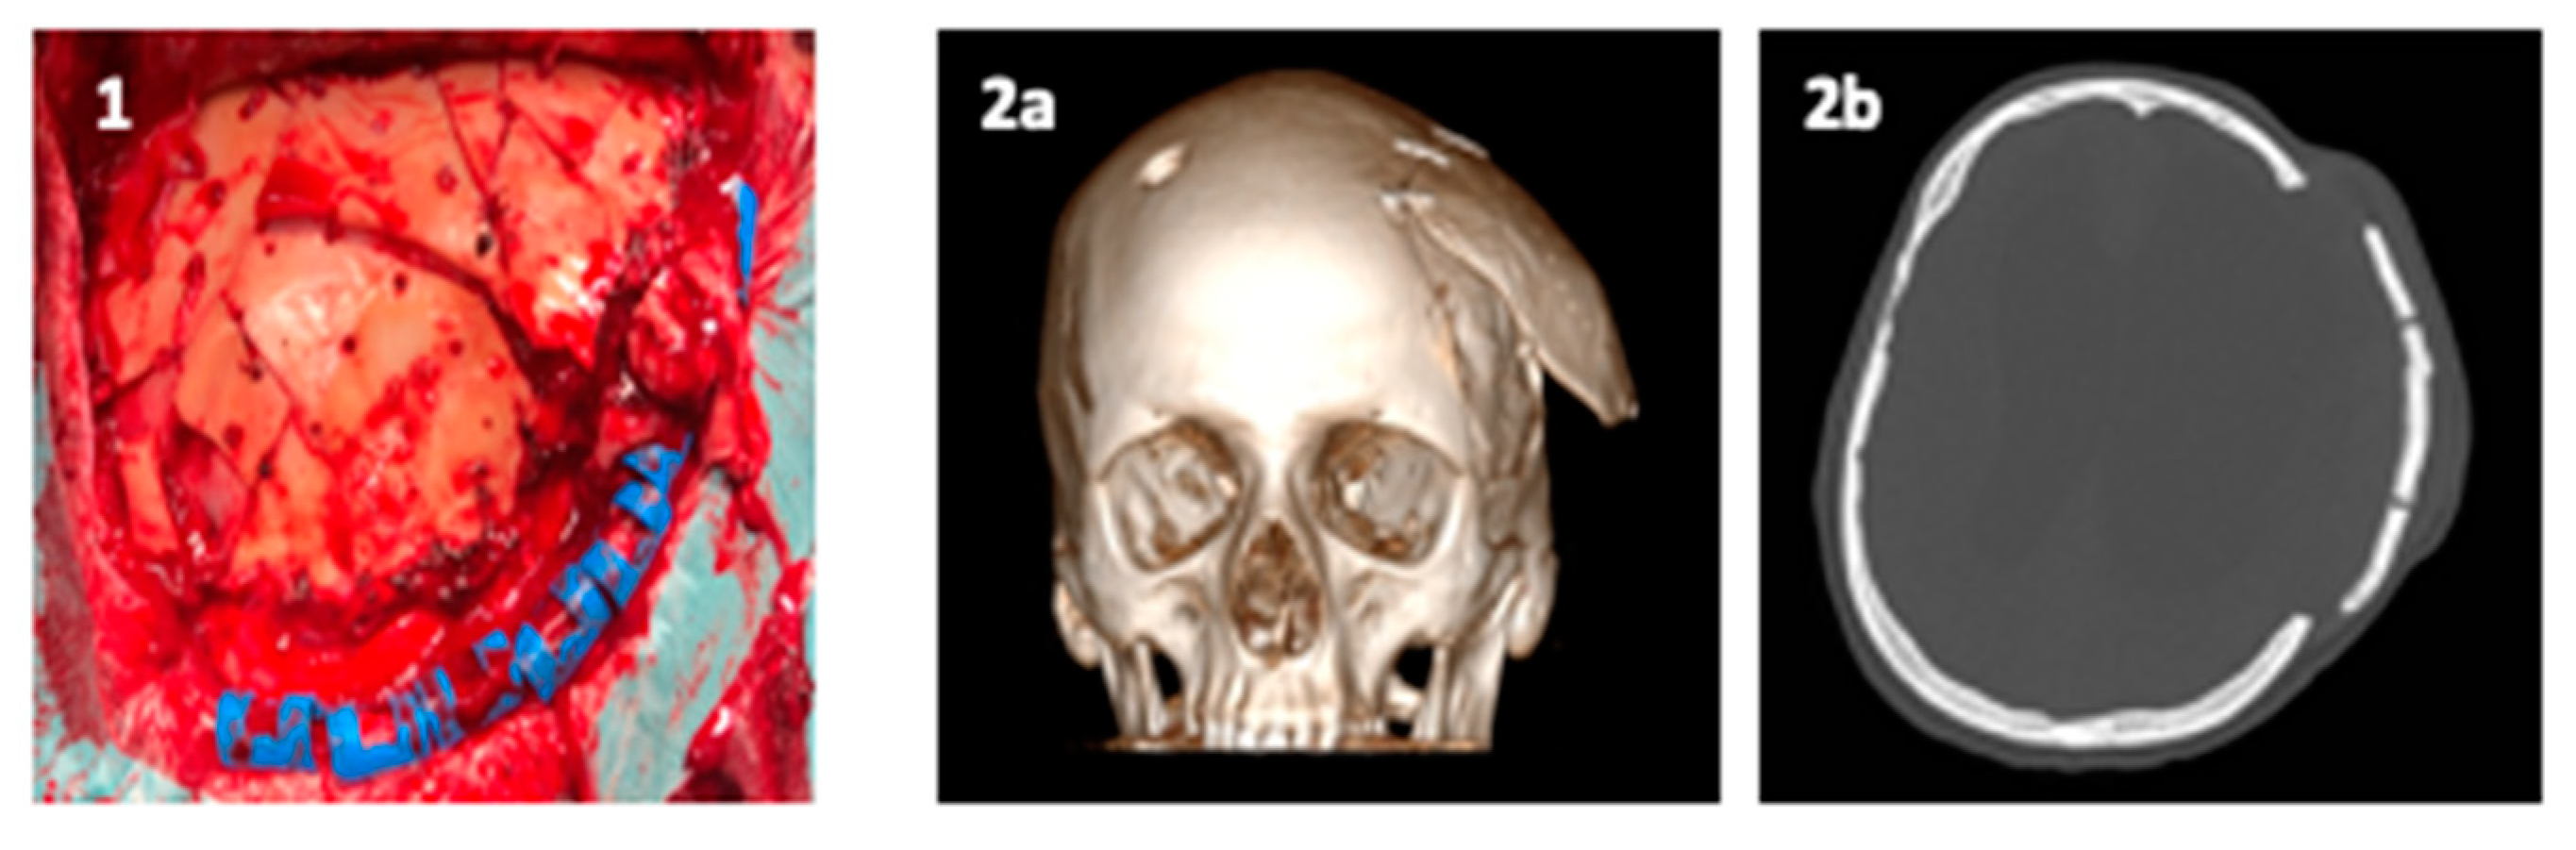

These 3D printing technologies are already used in clinical practice. One example is the one-step procedure that consists of a single surgical operation comprising a resection and reconstruction of cranial defects for lesions involving the skull base [71]. An example is reported in Figure 7:

Figure 7.

(a) Phantom model for virtual craniotomy; (b) 3D HR CT-scan of Phantom; (c) stealth navigation station; (d) post-operative axial CT-scan.

This procedure takes advantage of virtual 3D skull modelling techniques (Phantom model) (Figure 7a) by acquiring the patient’s high resolution (HR) CT-scan (Figure 7b) and creating a tailored cranioplasty, which reproduces an accurate reconstruction of the bone defect. To achieve better results modern stealth navigation assists the surgeon to perform the craniotomy and match to the custom-made cranioplasty (Figure 7c,d) [20].